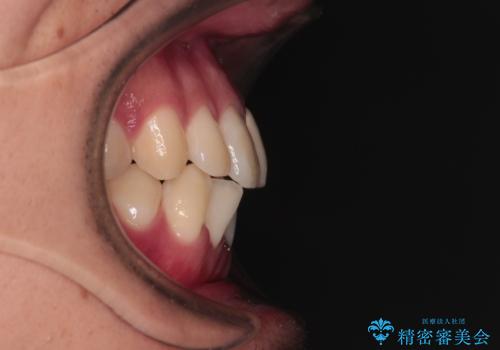

上下ともに歯列幅が狭く、その影響でデコボコになっていたため、ワイヤー装置を用いて歯列を側方に拡大しながら、デコボコを解消していくこととしました。

矯正治療後には気になっていた前歯をセラミッククラウンにし、自然な口元に仕上げることができました。